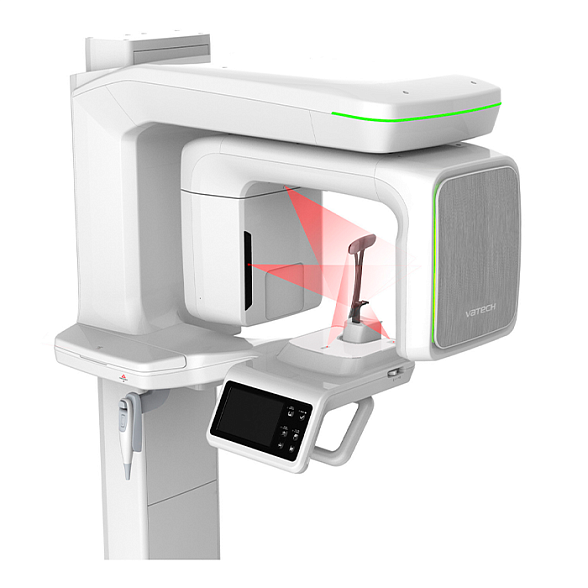

Carestream Dental CS 8100 3D - трехмерный томограф

Carestream Dental CS 8100 3D: Точная диагностика для современной стоматологии

Трехмерный дентальный томограф Carestream Dental CS 8100 3D — это решение для клиник, стремящихся к высочайшему качеству диагностики при оптимальных инвестициях. Аппарат сочетает в себе проверенную надежность, интуитивно понятное управление и передовые технологии визуализации, позволяя получать детальные 3D-снимки челюстно-лицевой области.

- Гибкость и универсальность: Аппарат поддерживает широкий диапазон настроек поля обзора (FOV) — от небольших участков до полного сканирования челюстно-лицевой области. Это позволяет минимизировать дозу облучения пациента, получая именно тот объем данных, который необходим для конкретного случая.

- Простота и скорость работы: Интуитивный интерфейс и автоматические настройки для стандартных протоколов съемки сокращают время обучения персонала и время самой процедуры. Получение и обработка 3D-модели занимают считанные минуты.

- Комфорт для пациента: Открытый дизайн томографа снижает ощущение замкнутого пространства, что особенно важно для пациентов с клаустрофобией. Быстрая съемка также способствует комфорту.

Технические характеристики Carestream Dental CS 8100 3D

| Параметр | Характеристика |

|---|---|

| Тип аппарата | Конусно-лучевой компьютерный томограф (КЛКТ) |

| Производитель / Бренд | Carestream Dental (США) |

| Напряжение питания | 220-240 В, 50/60 Гц |

| Поле обзора (FOV) | Широкий выбор, от 5x5 см до 17x13.5 см (зависит от модификации и настроек) |

| Разрешение вокселя | От 75 мкм (зависит от выбранного режима и FOV) |

| Напряжение на трубке | 60-90 кВ (регулируемое) |

| Ток на трубке | До 15 мА (регулируемый) |

| Время сканирования | От 4 до 20 секунд (в зависимости от режима и области) |

| Детектор | Плоскопанельный цифровой детектор |

| Программное обеспечение | Carestream Imaging Software (входит в комплект) |

| Формат данных | DICOM, JPEG, TIFF, AVI, BMP |

| Габариты (приблизительно) | Высота: ~210 см, Ширина: ~180 см, Глубина: ~140 см (могут варьироваться) |

| Вес (приблизительно) | Около 450 кг |